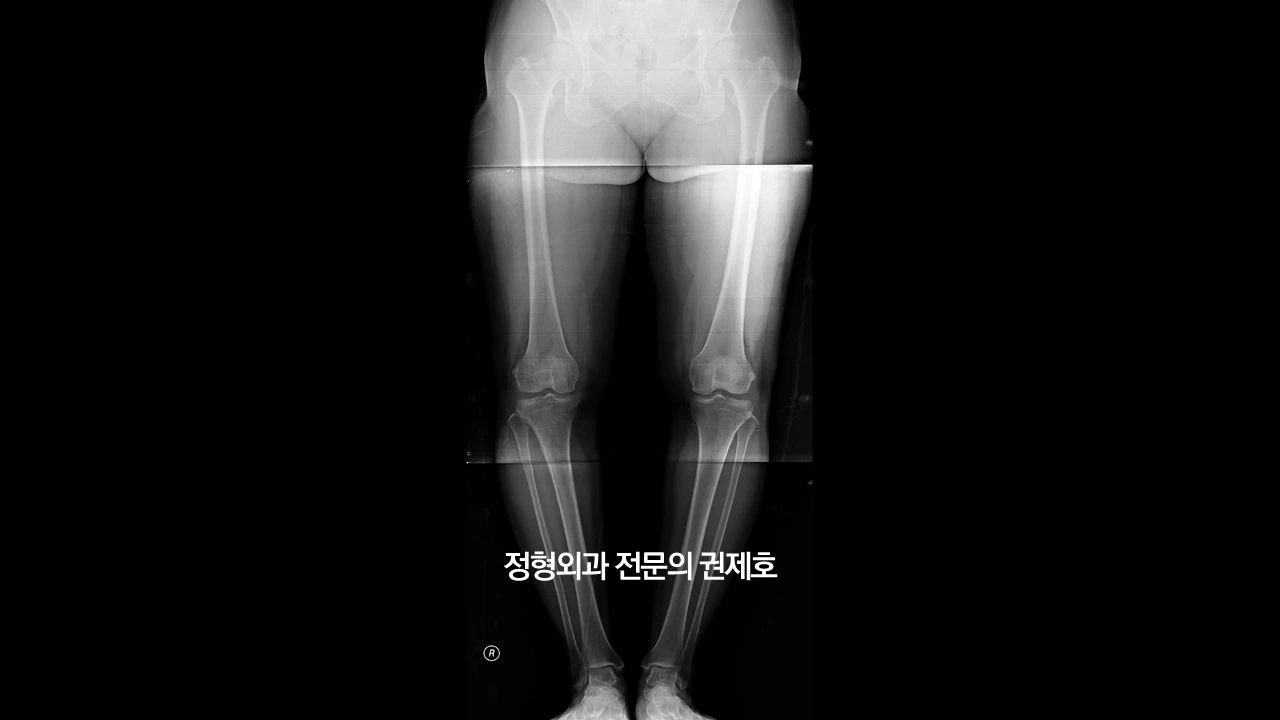

제가 가장 중요하게 여기는 하지 정렬 검사 사진입니다. 보시면 무릎이 많이 휘어 있는 것을 아실 수 있습니다. 바로 오다리입니다. 아마도 어릴 적부터 원래 오다리였다고 사료되며, 관절염으로 진단받고 관리는 하였으나 아마도 기존에 있던 휜다리가 증상 악화의 요인이 아닐까 생각하며, 비교적 젊은 나이이고, 다른 이상 소견이 있는지 확인하기 위해 MRI 검사를 진행했습니다.